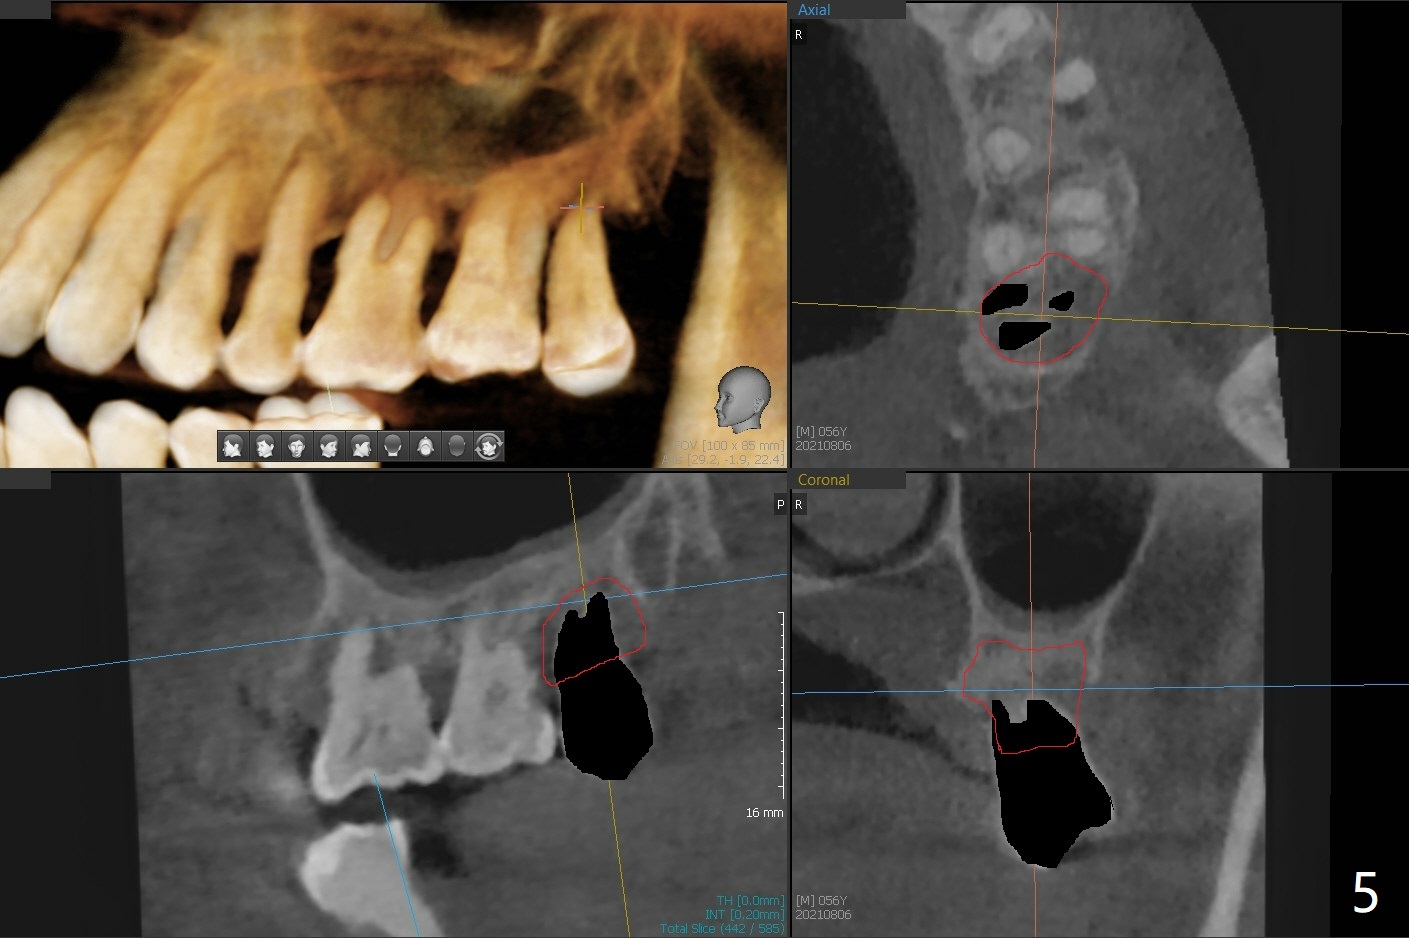

56岁男几十年拒绝牙周炎治疗,也不愿意拔除所有牙齿做全口植牙修复。17,18号牙自行脱落,现在要求拔除16,19;18,19种植(图一),后者牙龈厚(双箭头),但是18号牙骨质高度不足(图二),勉强植入5x7.3毫米植体。15,16骨质吸收严重(图三),16,19拔除,局部深洗后(图四:黑色),为了延长15号牙使用期,16号牙牙槽窝植骨(图五:红色)。19号牙种植徒手,因为邻牙(包括20,21号牙))松动,做导板不准确,钻洞使用环形钻头(图六),保留骨塞(bone plug),用于18号牙骨质高度骨块移植。19号牙拔除后,往远中18牙位做潜行分离(图七:黑色)。19种植(绿色),基台(粉红色),骨粉(圆圈),临时牙冠(白色),16号牙粘性骨粉植骨(红色),PRF,Cytoplast覆盖(白线),缝合。从19号牙钻洞取来的骨塞,塞入18号牙潜行分离处(图八);利用临时牙冠和22号牙以及钢丝,树脂固定20,21号牙(蓝色),并且降低咬合(*)。最后,用螺钉固定骨塞(图九:深蓝色)。